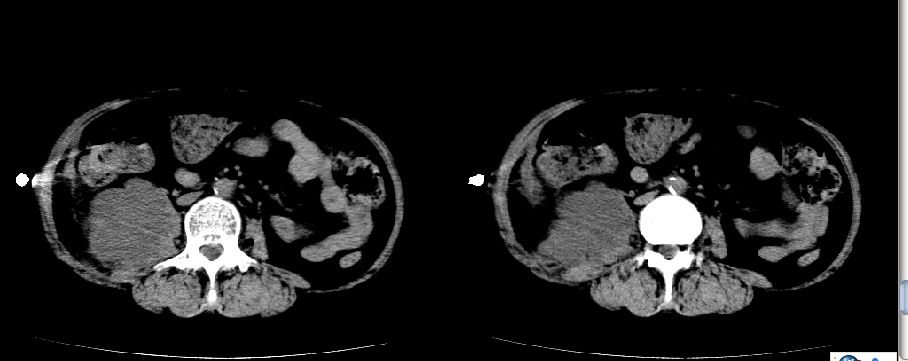

以下是引用liuyue在2008-7-19 10:17:00的发言:[br]考虑:1.肾周脓肿,肾实质、腰大肌及侧腹壁均受累及。 2.右肾囊肿。[br]建议:强化扫描,除外肾癌之可能。[br]

以下是引用zhengfaming在2008-7-19 14:48:00的发言:[br]右肾脓肿并感染可能性大,建议增强

以下是引用江广1996在2008-7-19 10:48:00的发言:[br]先考虑右侧肾周感染脓肿形成并累及腰大肌,右肾前侧有病灶考虑囊肿。